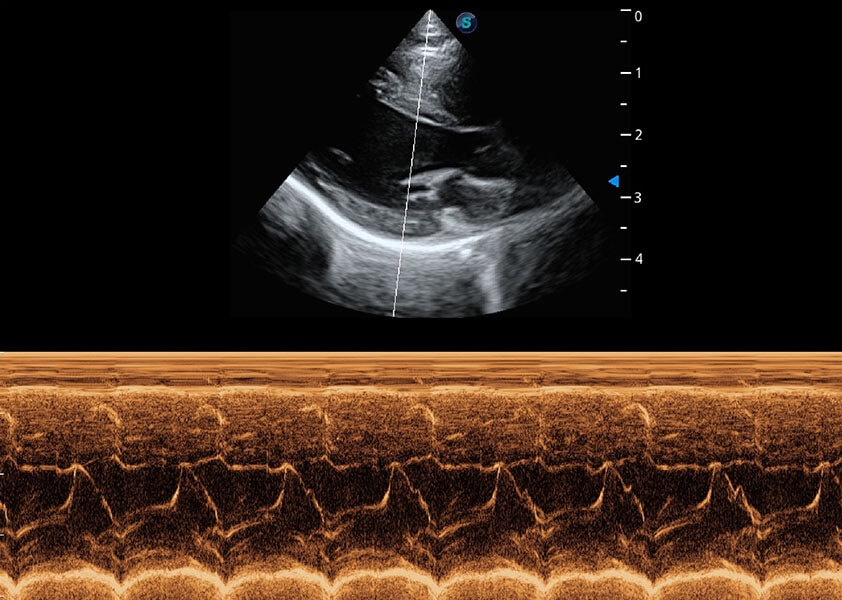

• AMM 解剖M型

通过360度任意调节3条M型取样线,在同一心动周期上观察心脏不同位置的运动曲线,得到准确的心功能测量数据,有效评估心肌运动及左心室功能。

(犬)心脏组织多普勒

(猫)二尖瓣M型